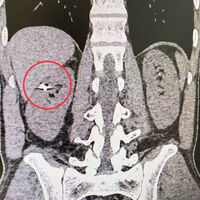

35-летний пациент получил травму около года назад, кусок металла размером 1 см прошел через печень и вонзился ему в почку. В ходе обследования медики обнаружили инородное тело в паренхиме – части органа, который фильтрует кровь. Было принято решение о проведении хирургического вмешательства.

«По данным компьютерной томографии, мы зафиксировали осколок в верхней части правой почки. Печень была тесно припаяна к почке, и извлечение осколка могло привести к серьезному кровотечению и потере органа. Мы сделали резекцию почки, причем лапароскопическим методом, и извлекли осколок», — рассказал заведующий урологическим отделением больницы Селим Везирханов.